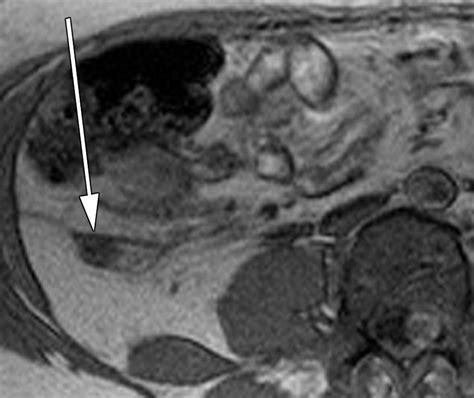

It is important to note that the location of the pain may shift as the pregnancy progresses. In the first trimester, the pain is usually in the lower right abdomen. However, as the uterus enlarges, the pain may be felt higher up in the abdomen.

• appendix location during pregnancy